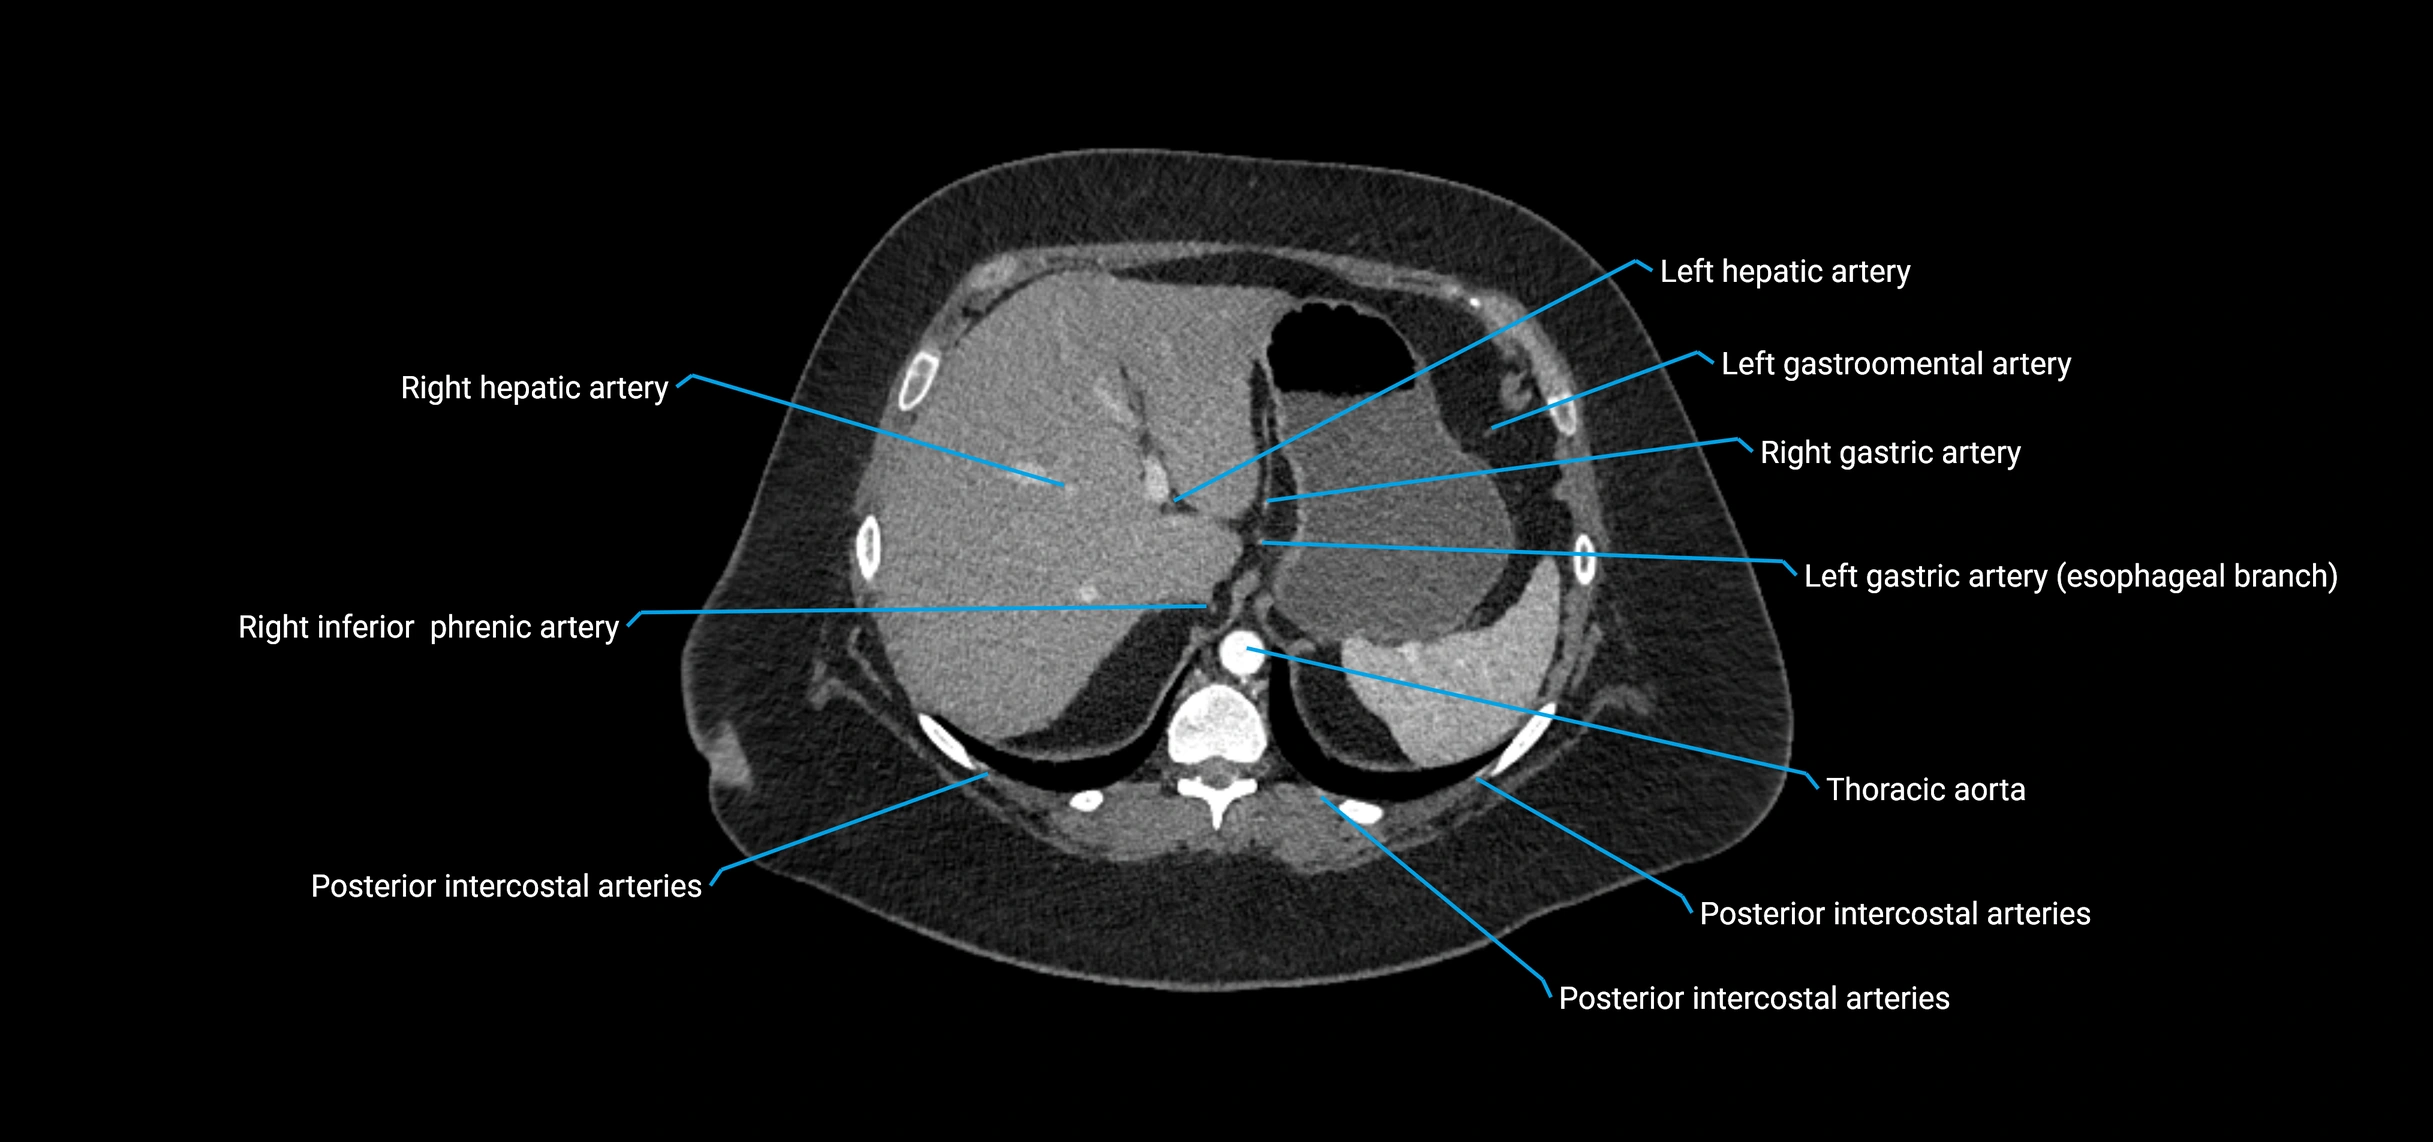

CT Appearance

Non-contrast CT:

• Appears as a tubular soft tissue structure anterior to vertebral bodies

• Calcified atherosclerotic plaques appear as hyperdense foci along the wall

• Useful for screening abdominal aortic aneurysm (AAA) size and mural calcification